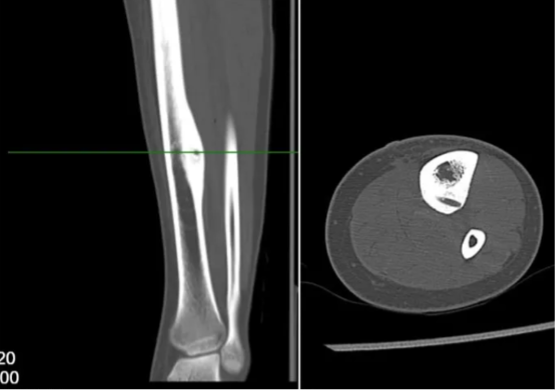

男性,17岁,因“左小腿疼痛10月余”就诊,患者10月前无明显诱因开始出现间歇性疼痛不适,夜间疼痛明显,口服塞来昔布可以缓解,逐渐加重。于当地医院就诊,行胫骨X线、CT及MRI检查,诊断为骨样骨瘤,当地医生无法确定,遂介绍至我院就诊。术前考虑患者为皮质型骨样骨瘤,瘤巢刺激骨皮质,胫骨内侧骨皮质增厚伴瘤巢形成,疼痛较为明显,但局部骨质太硬,单纯射频消融可能无法奏效,热量无法传导,导致消融范围失效,遂考虑采用导航下行左侧胫骨病灶超声骨刀磨除术的策略,采用水木天蓬超声骨刀铣刀头搭载Suretack连接S8导航系统。术后第二天患者自诉原有夜间疼痛有缓解,术后一个月基本感觉不到原来的疼痛。术后复查CT可见骨内明显的磨除隧道。

图6:术前左侧胫骨中下段影像检查提示骨皮质增厚

图9:术后复查CT见超声骨刀磨除的隧道